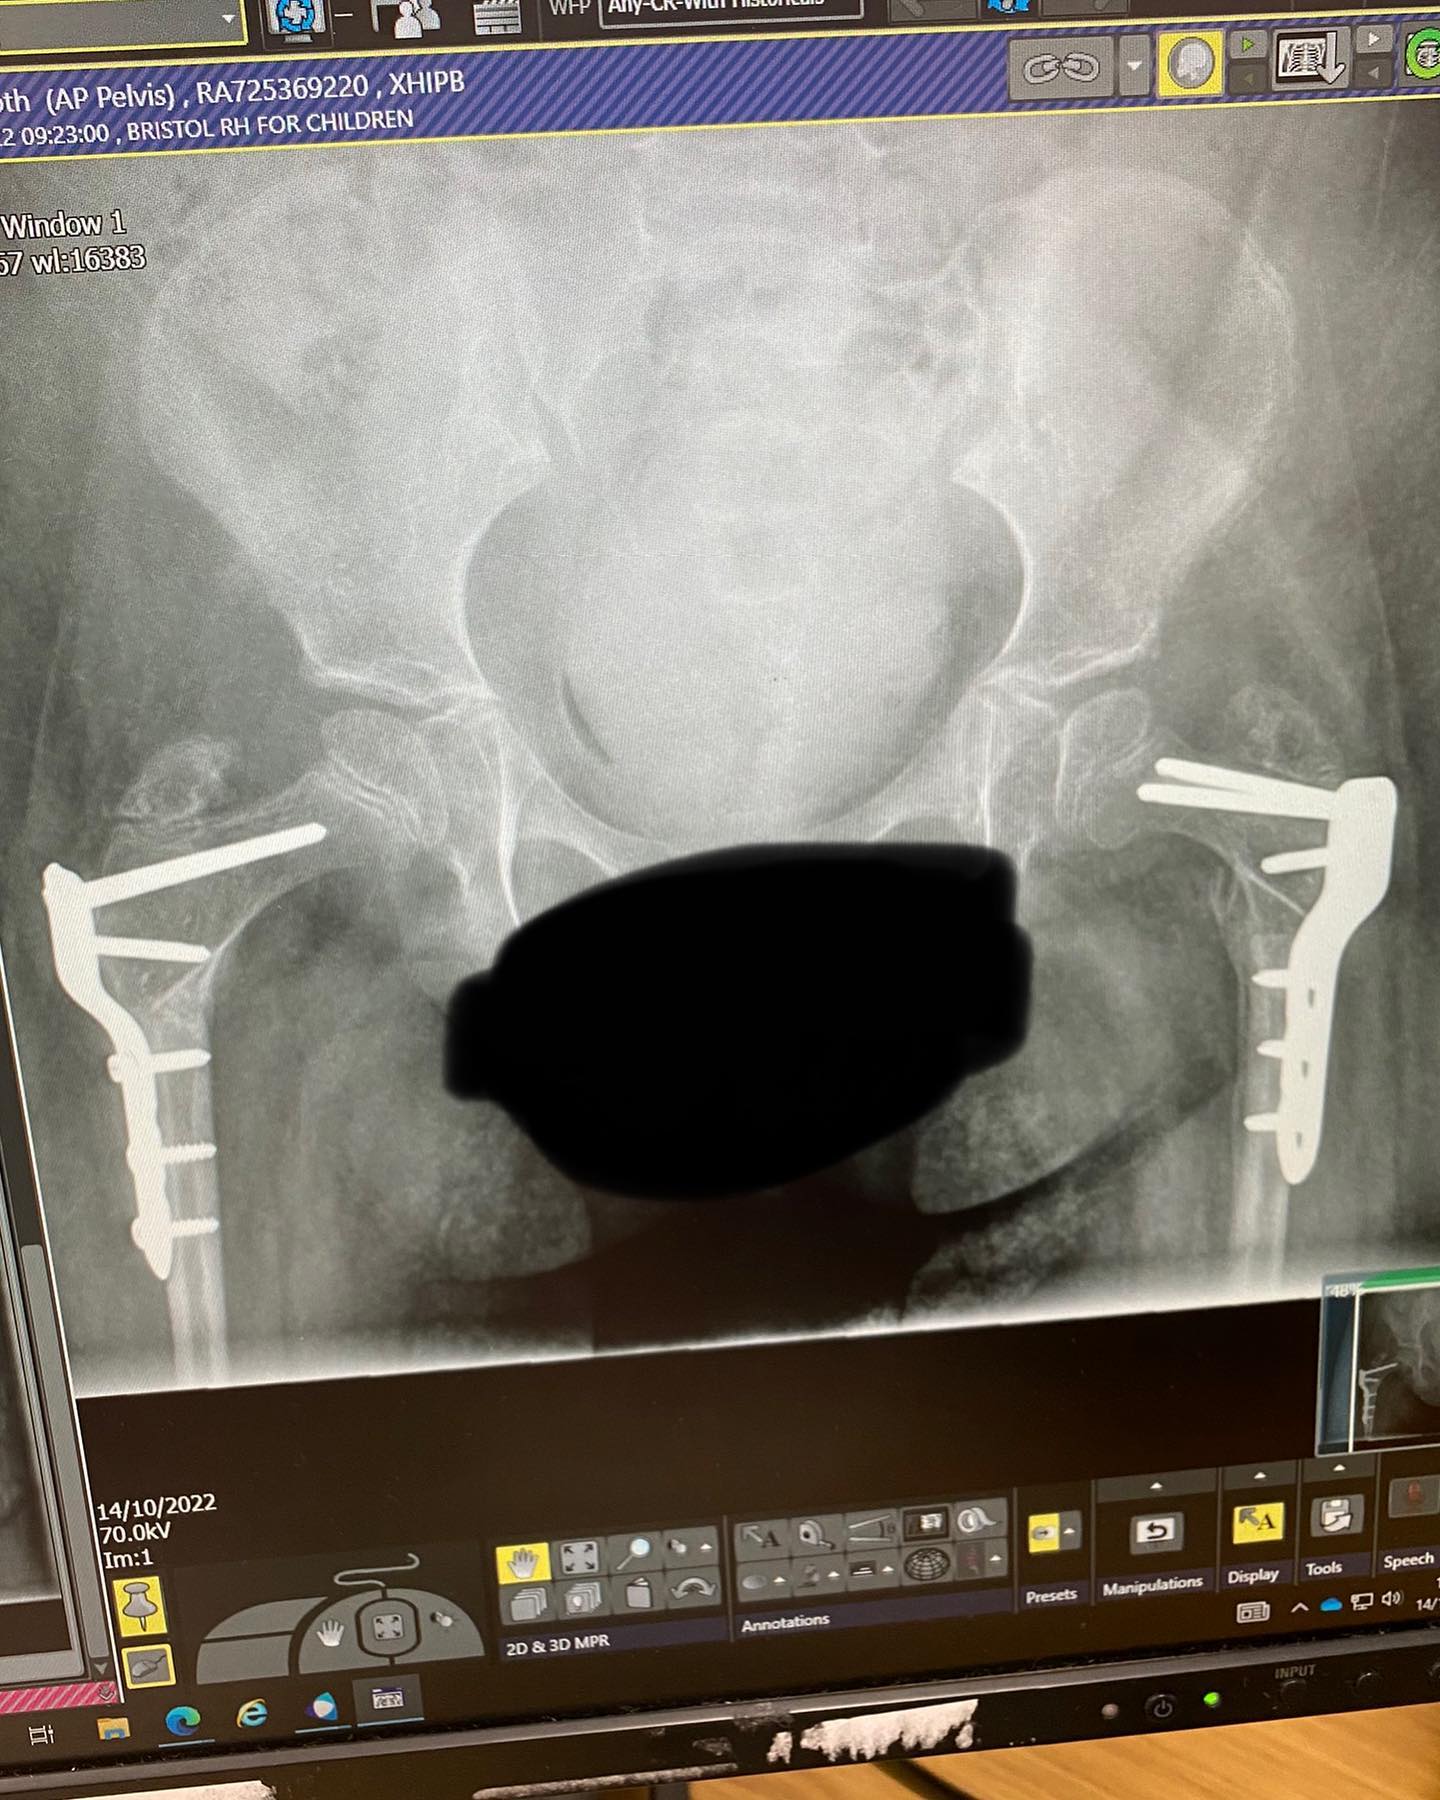

Originally, I saw this machine as something that may help Edith to walk independently, simulating steps, but it’s become more and more clear that this will more than likely not be the case (although never say never!). I was also aware of the health benefits that this piece of kit would bring and over the last five years this has been the main game changer for Edith. Since crowdfunding for the last Innowalk, Edith has been diagnosed with Osteopenia (low bone density) along with wedge fractures in her spine; read about this here( Bone Density ) and the main reason for this is lack of exercise and normal movement of the body. Osteopenia is the pre-requisite to osteoporosis and sadly this is likely to be a forgone conclusion for Edith, but with the Innowalk it can help to keep Edith's bones as strong as possible by creating that all important simulated exercise. As we all know, exercise is responsible for releasing endorphins and therefore keeping Edith happy and content despite her struggles. Exercise is also vital to keep the heart and lungs healthy throughout life and with Edith already having a healthy heart and lungs that need a bit of TLC following a few collapses over the years, this is another important factor. In June 2022 Edith underwent major orthopaedic surgery to reconstruct both of her hips. The top of her femur bones had not developed into the hip sockets properly and to correct this she needed to have both of her femur bones broken and repositioned into her hip sockets with pins and plates added to secure them into place; the surgery took nine hours and was the biggest thing Edith has ever had done. Edith’s surgeon has over compensated the angle to hopefully avoid any further surgery being needed but as Edith doesn’t walk this increases the risk of repeated surgery. The movement that the Innowalk will give will aid the further moulding of the hip bone into the socket and will go a long way in keeping Edith out of pain and needing further intervention. With all of this in mind, I’m sure you can appreciate how desperate I am to secure another Innowalk for Edith.